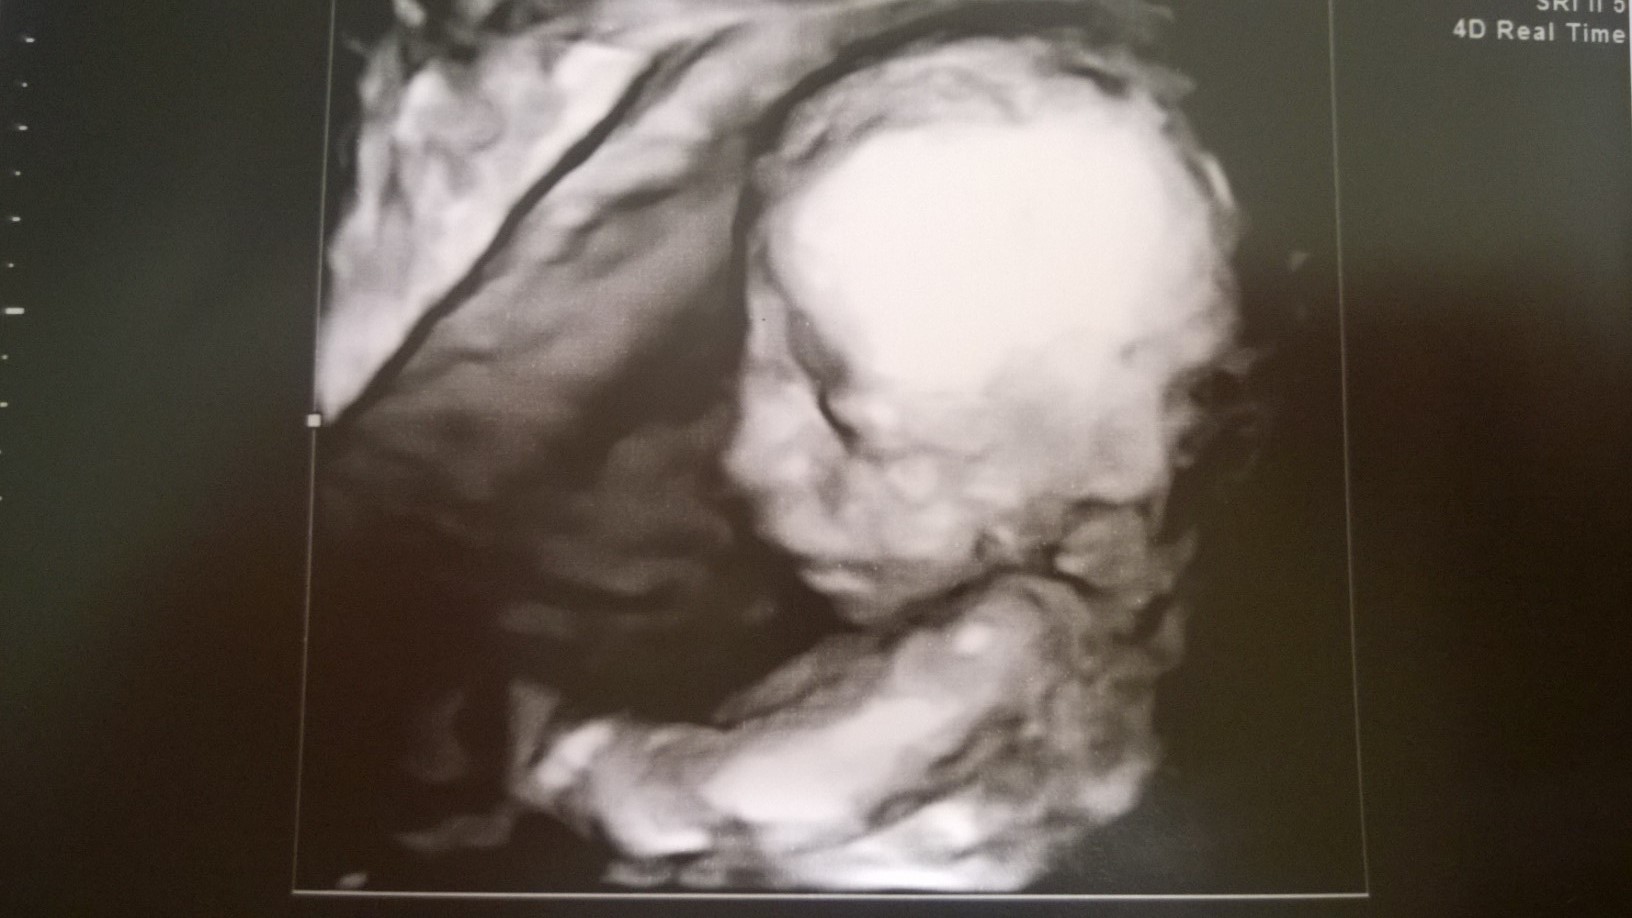

En ole yhtään ennättänyt käydä koko foorumilla pitkään aikaan. Sen verran ajattelin päivitellä kuulumisia, että meillä oli tänään rakenneultra (rv 19+5) ja pieni poikahan sieltä löytyi viuhtomasta. Kovasti koitti piilotella kasvojaan käden takana, mutta lopulta näytti naamansakin. Kaikki rakenteet oli siellä missä piti ja hyvältä näytti kaikin puolin. Neljän viikon kuluttua on seuraava ultra, koska olen seurannassa verenpainetautini takia. Jotain hyötyä siitäkin taudista :)

jätkä.jpg